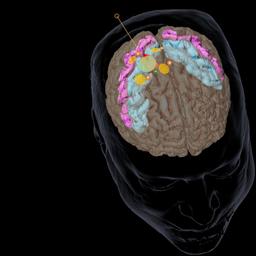

400.000 Menschen leiden in Deutschland an Parkinson, der zweithäufigsten neurodegenerativen Erkrankung nach Alzheimer. An neuen Medikamenten wird intensiv geforscht - mit positiven Ergebnissen. Von U. Till und M. Janning. mehr